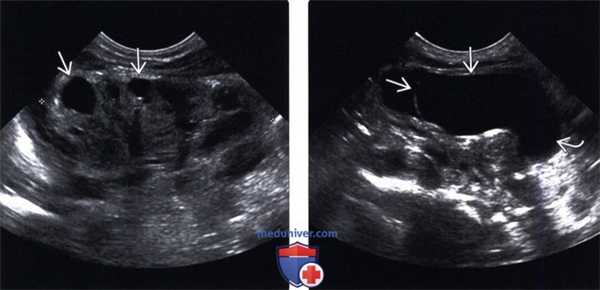

(Левый) На продольном УЗ срезе визуализируется две почечные лоханки, разделенные почечной паренхимой.

(Правый) На продольном УЗ срезе визуализируются выходящий из почки раздвоенный мочеточник. Гидронефроз в верхней половине почки, в нижней половине также наблюдается небольшое расширение, связанное с пузырно-мочеточниковым рефлюксом.